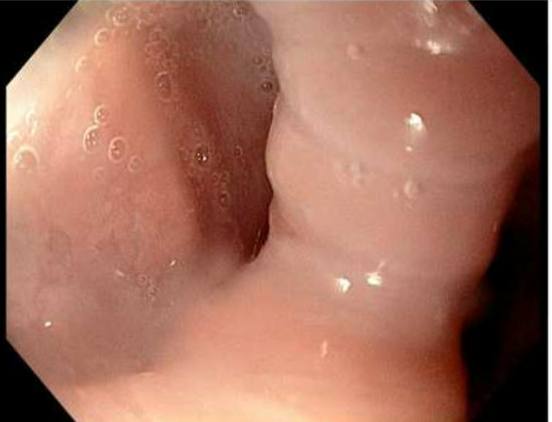

Figure 7: Post-procedure gastrografin swallow study showing mild persistence of Zenker diverticulum without an air leak.

Figure 7

The patient remained in the hospital overnight for monitoring and received a gastrografin swallow study the following day that showed no leak was present (Figure 7). She was discharged one day following her Z-POEM procedure and advised to continue a liquid diet for three days and a soft diet until her outpatient follow-up visit in 4 weeks. A month later, in the outpatient clinic the patient reported improved dysphagia with minimal discomfort. It was recommended for the patient to trial foods prior to her next visit that she has historically avoided due to her dysphagia. She is able to eat a normal diet currently without any pain or discomfort and she has been very pleased with the outcome of her procedure thus far.